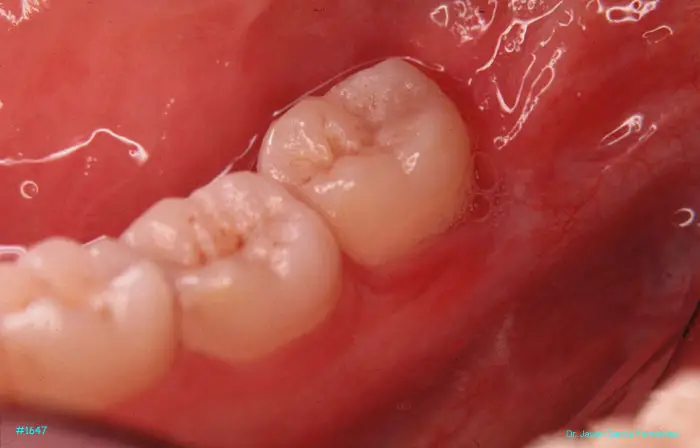

image 161